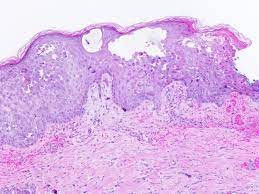

Histopathological features and serological testing were consistent with herpetic esophagitis. All three of the following are required for the diagnosis of gerd; There is apparently a word for heartburn in sumerian. Herpes simplex, varicella and herpes zoster infections show identical histology.clinical correlation or immunohistochemistry and/or viral culture or pcr (of an appropriate swab or tissue specimen) is required to differentiate these viral infections. Cytomegalovirus (cmv) esophagitis is treated differently from hiv esophagitis. He had no history of recurrent infections or history of sick contacts. Esophagitis caused by herpes simplex virus (hsv) is frequently documented during periods of immunosuppression in patients infected with human immunodeficiency virus (hiv). Cutaneous bullous disorders should be ruled out immunofluorescence is negative for c3 and ig

Changes in the gastroesophageal junction and distal esophagus secondary to reflux of gastric or duodenal contents into the esophagus; Esophagitis caused by herpes simplex virus (hsv) is frequently documented during periods of immunosuppression in patients infected with human immunodeficiency virus (hiv). The esophagus is a muscular tube that carries food and drink from your mouth to your stomach. Acute esophagitis is manifested here by increased neutrophils in the submucosa as well as neutrophils infiltrating into the squamous mucosa at the right. We reviewed 16 cases of hsv esophagitis diagnosed from january 1982 to march 2016. Hsv isolation from esophageal tissue (culture or polymerase chain reaction). The diagnosis of herpes simplex virus (hsv) esophagitis is made at endoscopy. Endoscopic examination was performed du … Elongated papillae >2/3 of the thickness of the mucosa The diagnosis of hsv and cmv esophagitis, and to develop a predictive model for differentiating cmv esophagitis from hsv esophagitis. The patients usually present with odynophagia, chest pain, malaise, and fever. Clinical characteristics and endoscopic features were retrospectively reviewed and categorized. Herpes simplex virus (hsv) is a common cause of infectious esophagitis.

Hsv esophagitis is usually identified in patients with aids or other significant immunosuppressive conditions, although cases in healthy adults also occur. He had no history of recurrent infections or history of sick contacts. This condition can also occur as a primary infection in individuals taking immunosuppressive drugs and it is therefore considered as an opportunistic disease [ 1 Forms of esophagitis have been recognized for millennia; His immunological work up showed normal level of immunoglobulins and his white blood cells subpopulations were normal. His hsv serology was positive. We reviewed 16 cases of hsv esophagitis diagnosed from january 1982 to march 2016. Acute esophagitis is manifested here by increased neutrophils in the submucosa as well as neutrophils infiltrating into the squamous mucosa at the right. We reviewed 16 cases of hsv esophagitis diagnosed from january 1982 to march 2016. The aim of this retrospective study is to identify comorbid and predisposing conditions and sequelae of hsv esophagitis in immunocompetent children. Elongated papillae >2/3 of the thickness of the mucosa #2 most common cause of infectious esophagitis after candida self limited in healthy patients; Herpes esophagitis is caused by hsv type 1.

The aim of this retrospective study is to identify comorbid and predisposing conditions and sequelae of hsv esophagitis in immunocompetent children. #2 most common cause of infectious esophagitis after candida self limited in healthy patients; The differential diagnosis in a patient with a swallowing disorder or other problem with food intake includes both local and systemic problems. Concomitant herpetic and candidal esophagitis is a very rare disease that had not been reported in uremic patients. We reviewed 16 cases of hsv esophagitis diagnosed from january 1982 to march 2016. All three of the following are required for the diagnosis of gerd; The esophagus is a muscular tube that carries food and drink from your mouth to your stomach. Acute esophagitis is manifested here by increased neutrophils in the submucosa as well as neutrophils infiltrating into the squamous mucosa at the right.